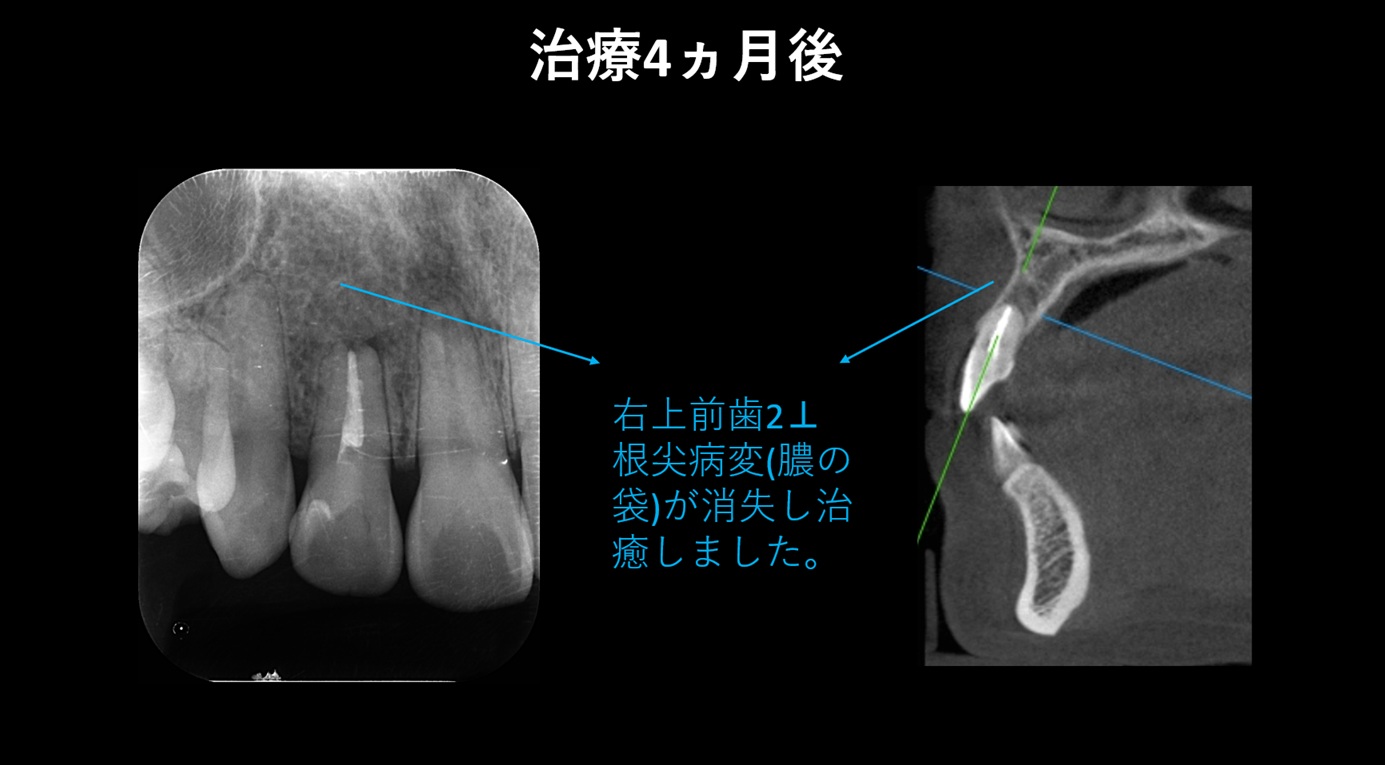

↑ 根管治療から 4か月後の経過観察 では、歯の根の先にあった 根尖病変は消失し、良好な治癒が確認できました。